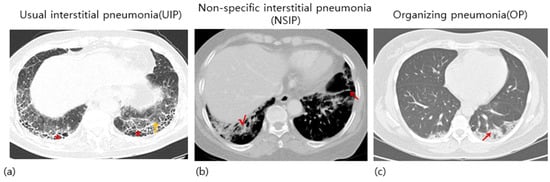

4. Histopathological Type of RA

- Chung, J.H.; Cox, C.W.; Montner, S.M.; Adegunsoye, A.; Oldham, J.M.; Husain, A.N.; Vij, R.; Noth, I.; Lynch, D.A.; Strek, M.E. CT features of the usual interstitial pneumonia pattern: Differentiating connective tissue disease–associated interstitial lung disease from idiopathic pulmonary fibrosis. Am. J. Roentgenol. 2018, 210, 307–313. [Google Scholar] [CrossRef]

- Dawson, J.; Fewins, H.; Desmond, J.; Lynch, M.; Graham, D. Predictors of progression of HRCT diagnosed fibrosing alveolitis in patients with rheumatoid arthritis. Ann. Rheum. Dis. 2002, 61, 517–521. [Google Scholar] [CrossRef]

- Park, J.H.; Kim, D.S.; Park, I.-N.; Jang, S.J.; Kitaichi, M.; Nicholson, A.G.; Colby, T.V. Prognosis of fibrotic interstitial pneumonia: Idiopathic versus collagen vascular disease–related subtypes. Am. J. Respir. Crit. Care Med. 2007, 175, 705–711. [Google Scholar] [CrossRef]

- Tsuchiya, Y.; Takayanagi, N.; Sugiura, H.; Miyahara, Y.; Tokunaga, D.; Kawabata, Y.; Sugita, Y. Lung diseases directly associated with rheumatoid arthritis and their relationship to outcome. Eur. Respir. J. 2011, 37, 1411–1417. [Google Scholar] [CrossRef]

- Nakamura, Y.; Suda, T.; Kaida, Y.; Kono, M.; Hozumi, H.; Hashimoto, D.; Enomoto, N.; Fujisawa, T.; Inui, N.; Imokawa, S. Rheumatoid lung disease: Prognostic analysis of 54 biopsy-proven cases. Respir. Med. 2012, 106, 1164–1169. [Google Scholar] [CrossRef] [PubMed]